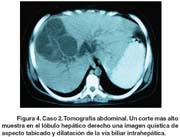

CASO 2: Mujer de 23 años procedente de Ancash. En la semana 32 de la gestación presentó dolor cólico epigástrico irradiado a hipocondrio derecho, asociado a náuseas y vómitos. Cuatro días después se produjo parto vaginal pretérmino luego del cual se hizo evidente una masa palpable dolorosa en hipocondrio derecho. Al día siguiente presentó ictericia leve. Se evaluó con ecografía y tomografía abdominal en las que se evidenció quiste complejo con tabiques internos en lóbulo hepático derecho. Posteriormente el dolor disminuyó y la ictericia desapareció. Llegó a Lima diez días post parto y fue admitida. Al examen se encontraba estable y afebril. No tenía edema, adenopatías, ictericia, ni estigmas hepáticos. El hígado era doloroso y se palpaba a ocho centímetros debajo del reborde costal con superfi cie regular. Los exámenes auxiliares se muestran en la tabla 2 y la tomografía en las figuras 3 y 4.